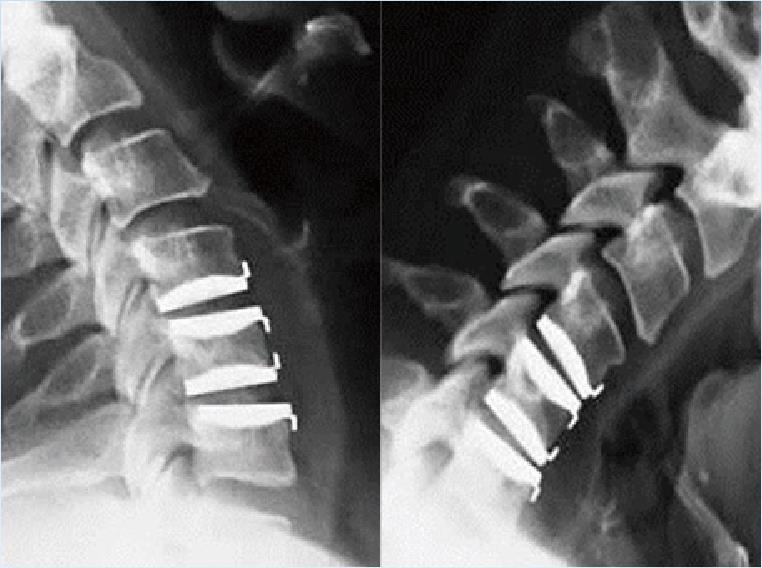

病例1:颈椎人工椎间盘置换术

颈前路C4-6椎间盘切除,Bryan人工椎间盘置换术,术后10年随访活动度良好。